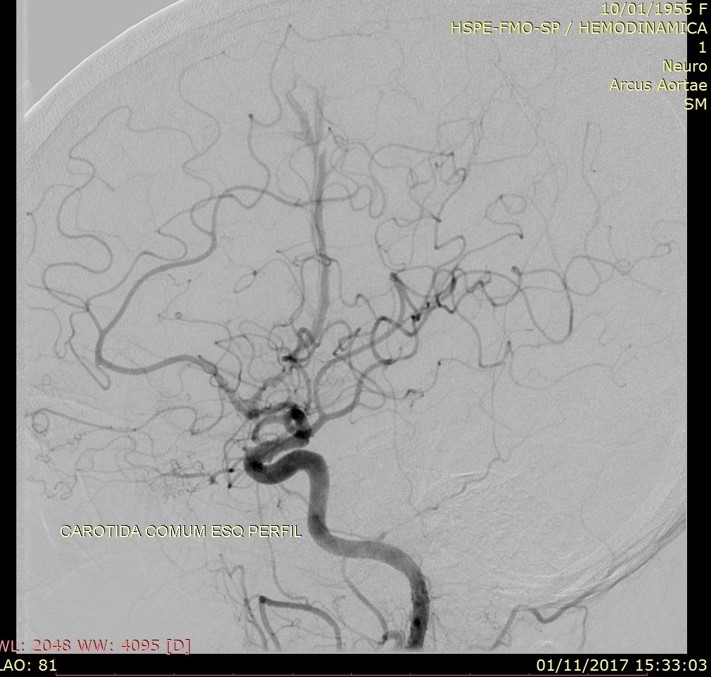

Discussão de tratamento de Fístula Arteriovenosa Dural grau I

Malformações artério venosas durais intracranianas - Discussão de caso fístula dural pós traumática grau I

Fístulas arteriovenosas durais (FAVDs) são lesões adquiridas, que consistem em uma ou mais conexões fistulosas no interior dos folhetos da dura-máter, envolvendo mais especificamente as paredes de um seio venoso dural ou as veias leptomeníngeas adjacentes.

Em 1995, Cognard et al. analisaram retrospectivamente 205 pacientes portadores de FAVDs, atendidos no período de 18 anos, em três grandes centros de referência no mundo. Algumas alterações e complementações foram propostas à classificação estabelecida anteriormente por Djindjian et al.  Na classificação publicada por Cognard et al., as lesões tipo I possuem drenagem diretamente para o interior de um seiovenoso dural, somente de forma anterógrada . As lesões tipo II são caracterizadas por elevada sobrecarga arterial e insuficiente drenagem venosa anterógrada. Ocorre, então, fluxo retrógrado ao longo do seio venoso.  Essa categoria é subdividida em três grupos,incluindo: tipo lIa com fluxo retrógrado somente no interior do seio venoso; tipo Ilb, com fluxo anterógrado no interior do seio venoso e refluxo para as veias corticais; e tipo lIa + b, com fluxo retrógrado para o seio e veias corticais. As lesões tipo III drenam exclusivamente para as veias corticais sem ectasia venosa. As lesões tipo IV drenam diretamente para as veias corticais que possuem ectasia venosa (dilatação maior que 5 mm de diâmetro). Finalmente, Cognard et al.acrescentaram um novo grupo, representado pelas lesões que drenam diretamente para as veias perimedulares espinhais, classificando-as como tipo V.